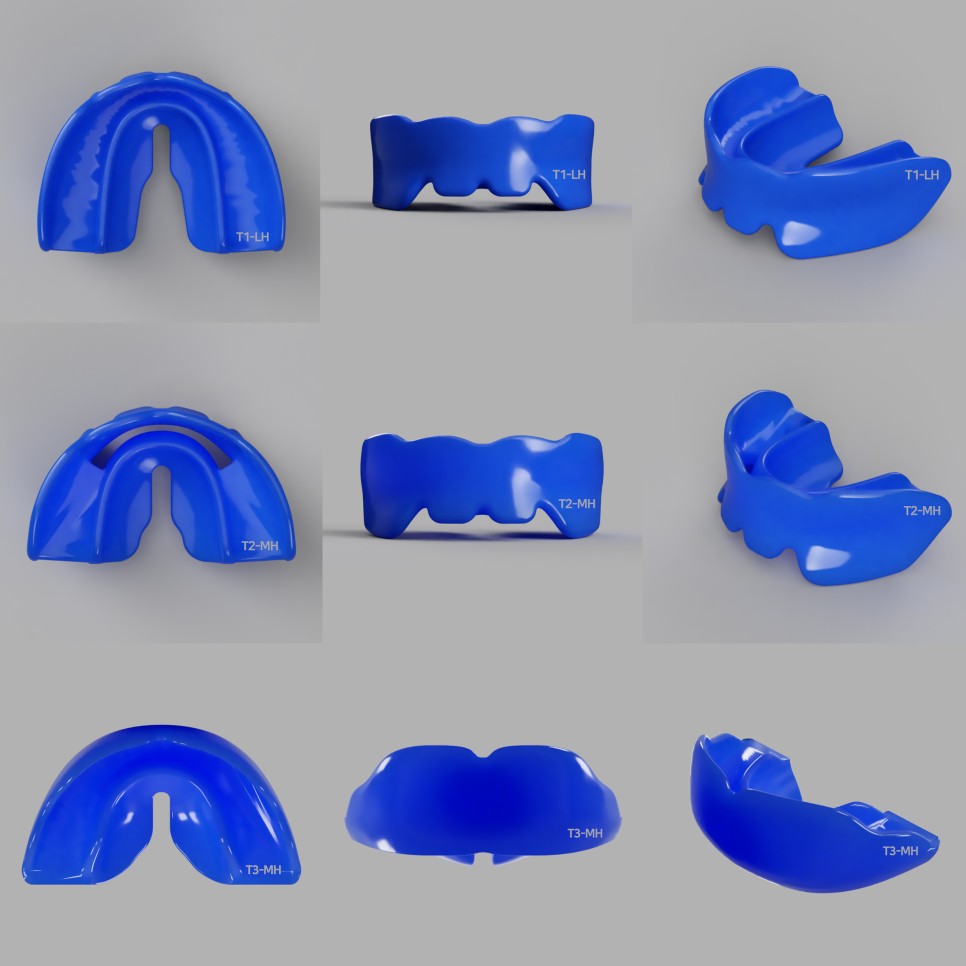

프리올소

뮤잉 방법은 구강근기능요법의 일종으로 구강 안에 구강근기능장치(프리올소)를 착용 후 혀,입술,뺨 등 구강주변근육의 기능을 향상 시켜주며 악성구강습관과 치열이 고르게 될 수 있도록 도와줍니다.

치열을 고르게 될 수 있도록 도와주는 경우는 유치가 빠지고 영구치가 나오는 성장기 제일 효과가 좋습니다.